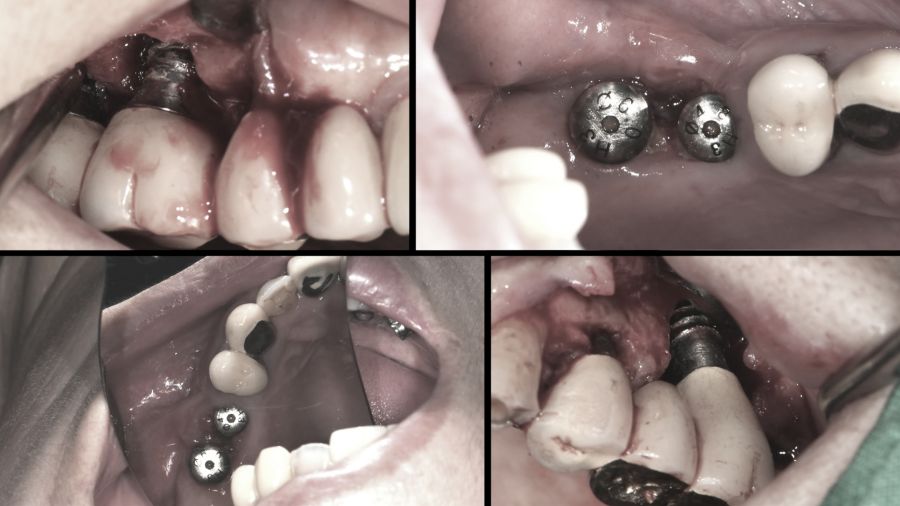

한 달 전부터 위쪽 어금니 임플란트에 통증을 느꼈다는 여성. 검사 결과 식립한 임플란트 고정체가 부러진 채 뼈에 박혀있는 상태였다. 실제로 통계에 따르면 임플란트 부작용 중에 나사 풀림과 파절이 약 49%로 1위를 차지한다.

임플란트의 나사가 풀리면 다시 조여주기만 하면 되지만 여성의 경우 나사가 잇몸에 고정된 채 부러져 제거하고 재식립 해야 하는 상황이다. 보철과 윤준호 교수는 임플란트를 제거하는 것은 임플란트를 식립하는 것보다 훨씬 어렵다고 말한다.

임플란트는 식립한 순간부터 주변 뼈와 유착이 이루어진다. 치주인대가 없이 나사못과 뼈가 바로 붙어 있기 때문에 제거 시 뼈 손상이 불가피하다. 따라서 신중하게 제거하지 않으면 상악동이 뚫리거나 하악의 경우 수많은 신경다발이 지나가기 때문에 신경 손상으로 마비, 통증 등을 유발할 수 있어 매우 신중해야 한다. 그렇다면 임플란트 제거술은 어떻게 진행되는 것일까? 임플란트 제거술과 나사 풀림과 파절이 발생하는 원인 및 임플란트를 망가트리는 습관 등을 자세히 알아본다.